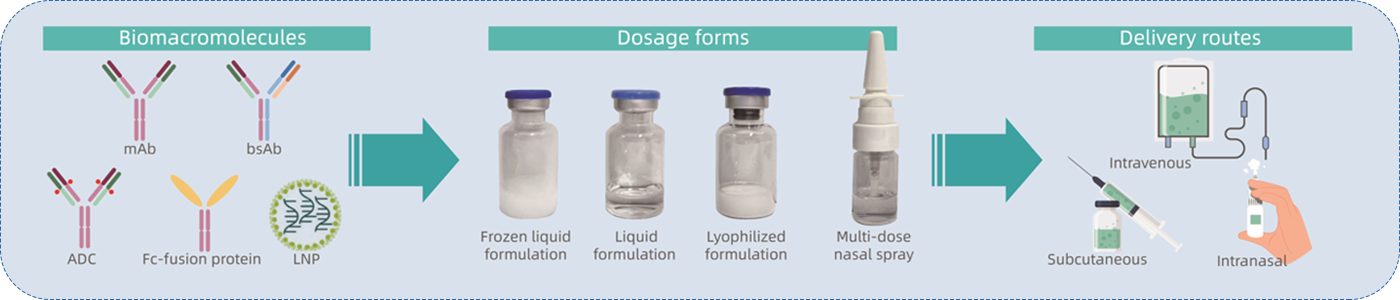

В· з¬јзҪ©з§Қз§ҚйҖҡдҫӢе’ҢжҢ‘жҲҳжҖ§еҲ¶еүӮзӯүејҖеҸ‘ пјҢпјҢ пјҢ пјҢпјҢеҰӮж¶ІдҪ“еҲ¶еүӮеҶ»е№ІеҲ¶еүӮгҖҒеӨҡеүӮйҮҸйј»е–·е’Ңй«ҳжө“еәҰж¶ІдҪ“еҲ¶еүӮзӯү

В· е…јйЎҫз§Қз§Қз»ҷиҚҜйҖ”еҫ„ пјҢпјҢ пјҢ пјҢпјҢеҰӮйқҷи„үжіЁе°„гҖҒзҡ®дёӢ/иӮҢиӮүжіЁе°„гҖҒйј»и…”зӯү

В· з¬јзҪ©з§Қз§ҚеҲҶеӯҗзұ»еһӢзҡ„еҲ¶еүӮејҖеҸ‘ пјҢпјҢ пјҢ пјҢпјҢ еҰӮеҚ•жҠ—гҖҒеҸҢжҠ—гҖҒиһҚеҗҲеҚөзҷҪгҖҒ еҒ¶иҒ”иҚҜзү© (ADCгҖҒRDCгҖҒAOCзӯү)гҖҒзәізұіи„ӮиҙЁдҪ“(mRNA-LNP)зӯү